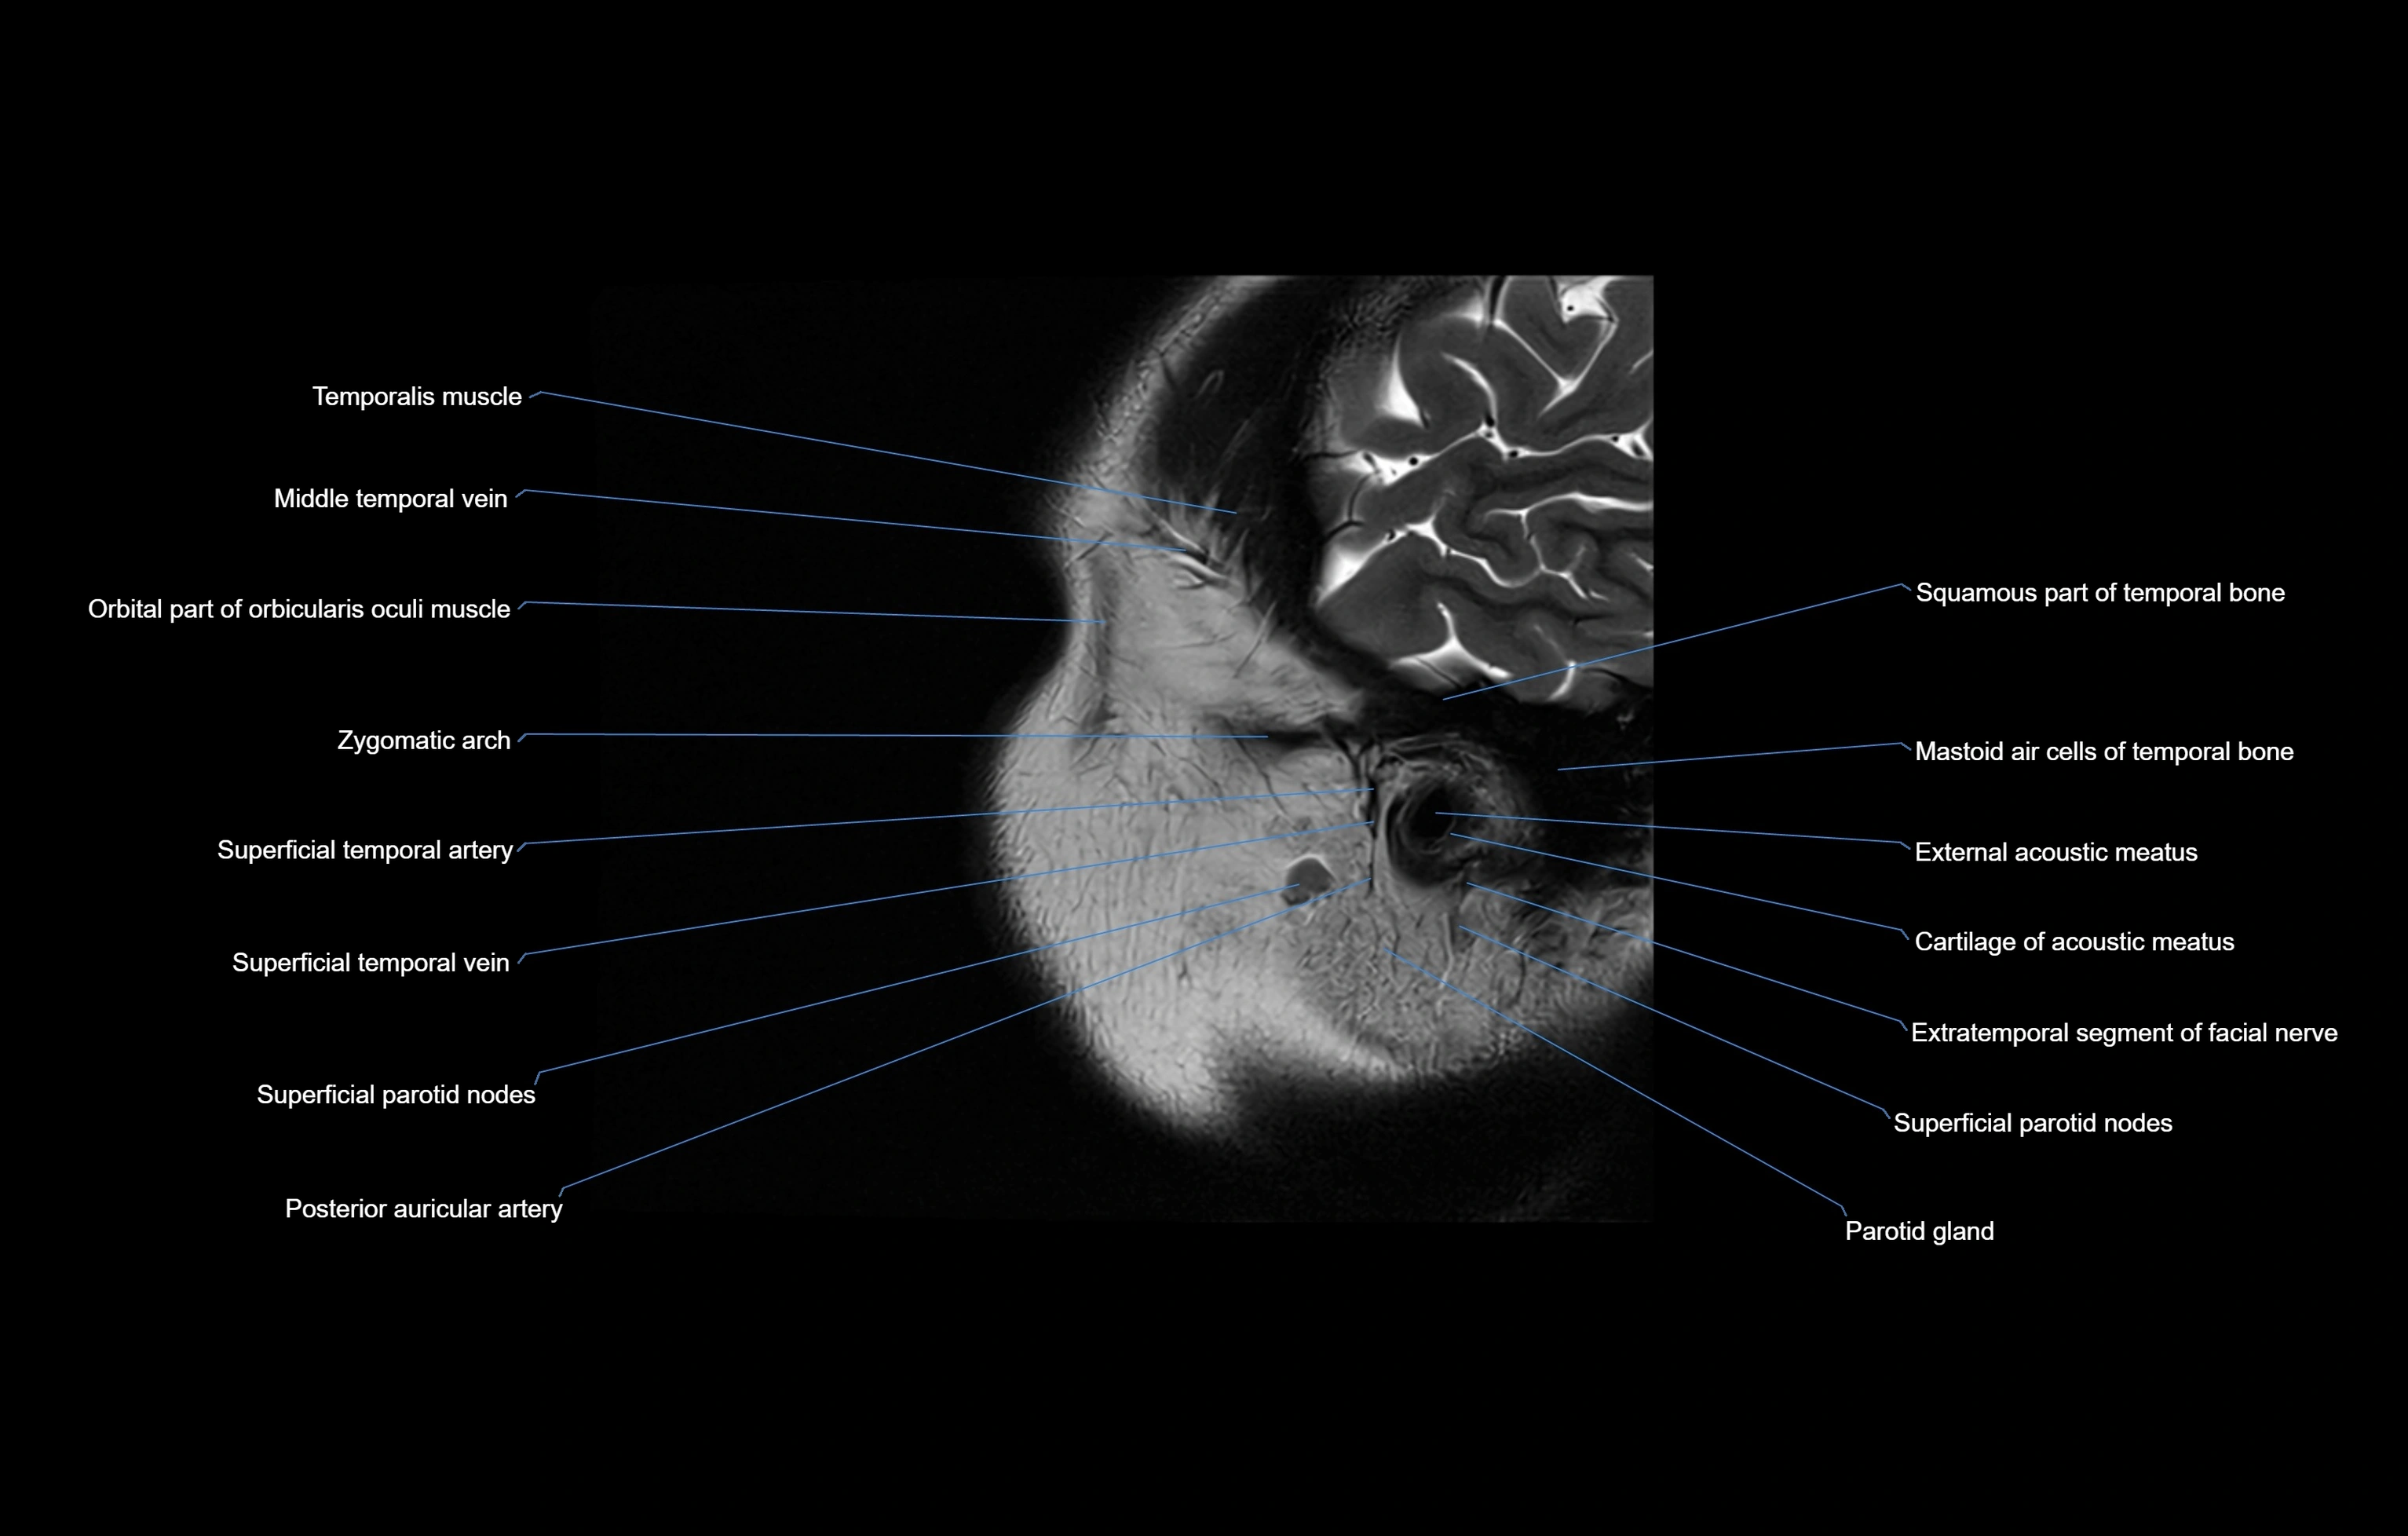

- External acoustic meatus

- Mastoid air cells

- Parotid gland

- Posterior auricular artery

- Squamous part of temporal bone

- Superficial parotid lymph nodes

- Superficial temporal artery

- Superficial temporal vein

- Temporalis muscle

- Zygomatic arch